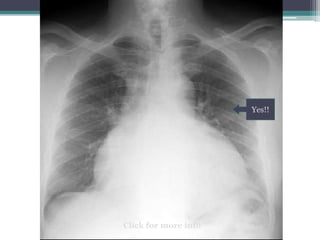

Can you see the pulmonary arteries on the

following radiograph?

Yes!!

Hilum overlay sign

โ€ข Heart is enlarged, but hilar vessels still visible

lateral to the cardiac silhouette

โ€ข This case is pericardial effusion